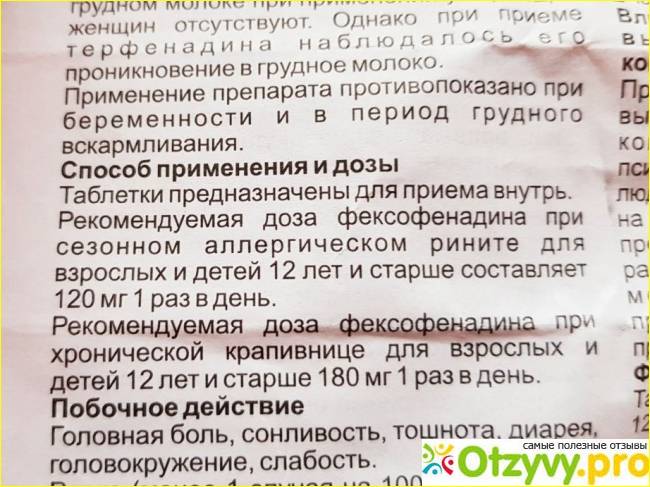

Реактивный приступ – не имеет систематического характера. Проявляется, как реакция на лекарства, которые не подходят животному.

Если приступ эпилепсии у кота был вызван назначением лекарства, которое ему не подошло, то схема лечения простая:

- выявить на какое лекарство аллергия;

- отменить прием препарата;